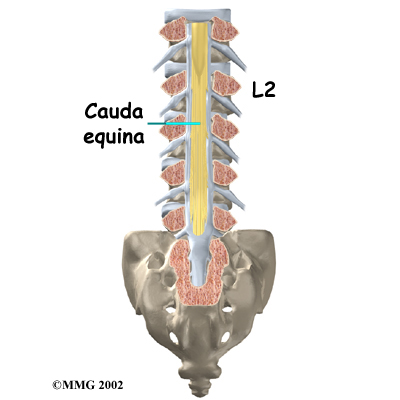

Each vertebra is formed by a round block of bone, called a vertebral body. A attaches to the back of the vertebral body. When the vertebrae are stacked on top of each other, these bony rings create a hollow tube. This tube, called the spinal canal, surrounds the as it passes through the spine. Just as the skull protects the brain, the bones of the spinal column protect the spinal cord.

The spinal cord only extends to L2. Below this level, the spinal canal encloses a bundle of nerves that goes to the lower limbs and pelvic organs. The Latin term for this bundle of nerves is , meaning horse's tail.